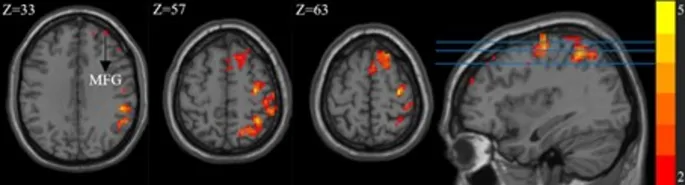

Рис. 1. Значение mALFF в группе IGD значительно повышено в области мозга. Черная стрелка указывает на среднюю лобную извилину, а синие горизонтальные линии представляют Z = 33, Z = 57 и Z = 63. MFG, средняя лобная извилина

По сравнению с группой HC, значения mALFF правой верхней тетрабоковой извилины, правой нижней тетрабоковой извилины, правой прецентральной извилины, правой надкраевой извилины, правой постцентральной извилины, правой дорсолатеральной верхней лобной извилины, правой дополнительной двигательной области (SMA) и правой средней лобной извилины (MFG) были значительно повышены в группе IGD (Рис. 1). В то время как значения mALFF левой верхней мозжечковой ножки, двусторонней извилины прямой, левой веретенообразной извилины, двустороннего полюса височной доли, левой парагиппокампальной извилины, левой орбитальной верхней лобной извилины и левой медиальной орбитальной верхней лобной извилины были значительно снижены в группе IGD (Рис. 2).